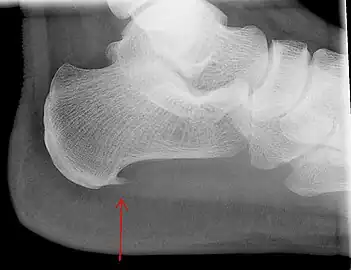

An incidental finding associated with this condition is a heel spur, a small bony calcification on the calcaneus (heel bone), which can be found in up to 50% of those with plantar fasciitis.[6] In such cases, it is the underlying plantar fasciitis that produces the heel pain, and not the spur itself.[13] The condition is responsible for the creation of the spur though the clinical significance of heel spurs in plantar fasciitis remains unclear.[12]

a)Ultrasonographic finding of plantar fasciitis b)normal sonographic finding Heel bone with heel spur

Heel bone with heel spur Thickened plantar fascia in ultrasound

Imaging

Medical imaging is not routinely needed. It is expensive and does not typically change how plantar fasciitis is managed.[15] When the diagnosis is not clinically apparent, lateral view X-rays of the ankle are the recommended imaging modality to assess for other causes of heel pain, such as stress fractures or bone spur development.[7]

The plantar fascia has three fascicles-the central fascicle being the thickest at 4 mm, the lateral fascicle at 2 mm, and the medial less than a millimeter thick.[18] In theory, plantar fasciitis becomes more likely as the plantar fascia's thickness at the calcaneal insertion increases. A thickness of more than 4.5 mm ultrasound and 4 mm on MRI are useful for diagnosis.[19] Other imaging findings, such as thickening of the plantar aponeurosis, are nonspecific and have limited usefulness in diagnosing plantar fasciitis.[13]